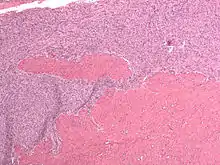

| Micrograph of a low-grade endometrial stromal sarcoma. H&E stain. | |

- Monotonous ovoid cells to spindly cells with minimal cytoplasm.

- Prominent arterioles. Angiolymphatic invasion common.

- Up to 10-15 mitotic figures per 10 HPF in most active areas.

- Tongue-like infiltration between muscle bundles of myometrium.